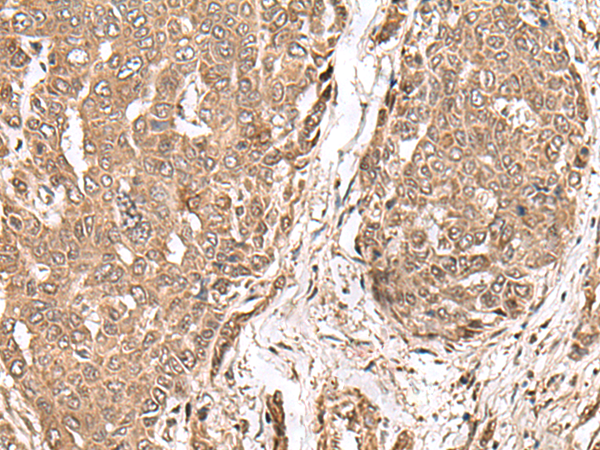

IHC positive control:

Human esophagus cancer and Human thyroid cancer

IHC Recommend dilution:

50-300